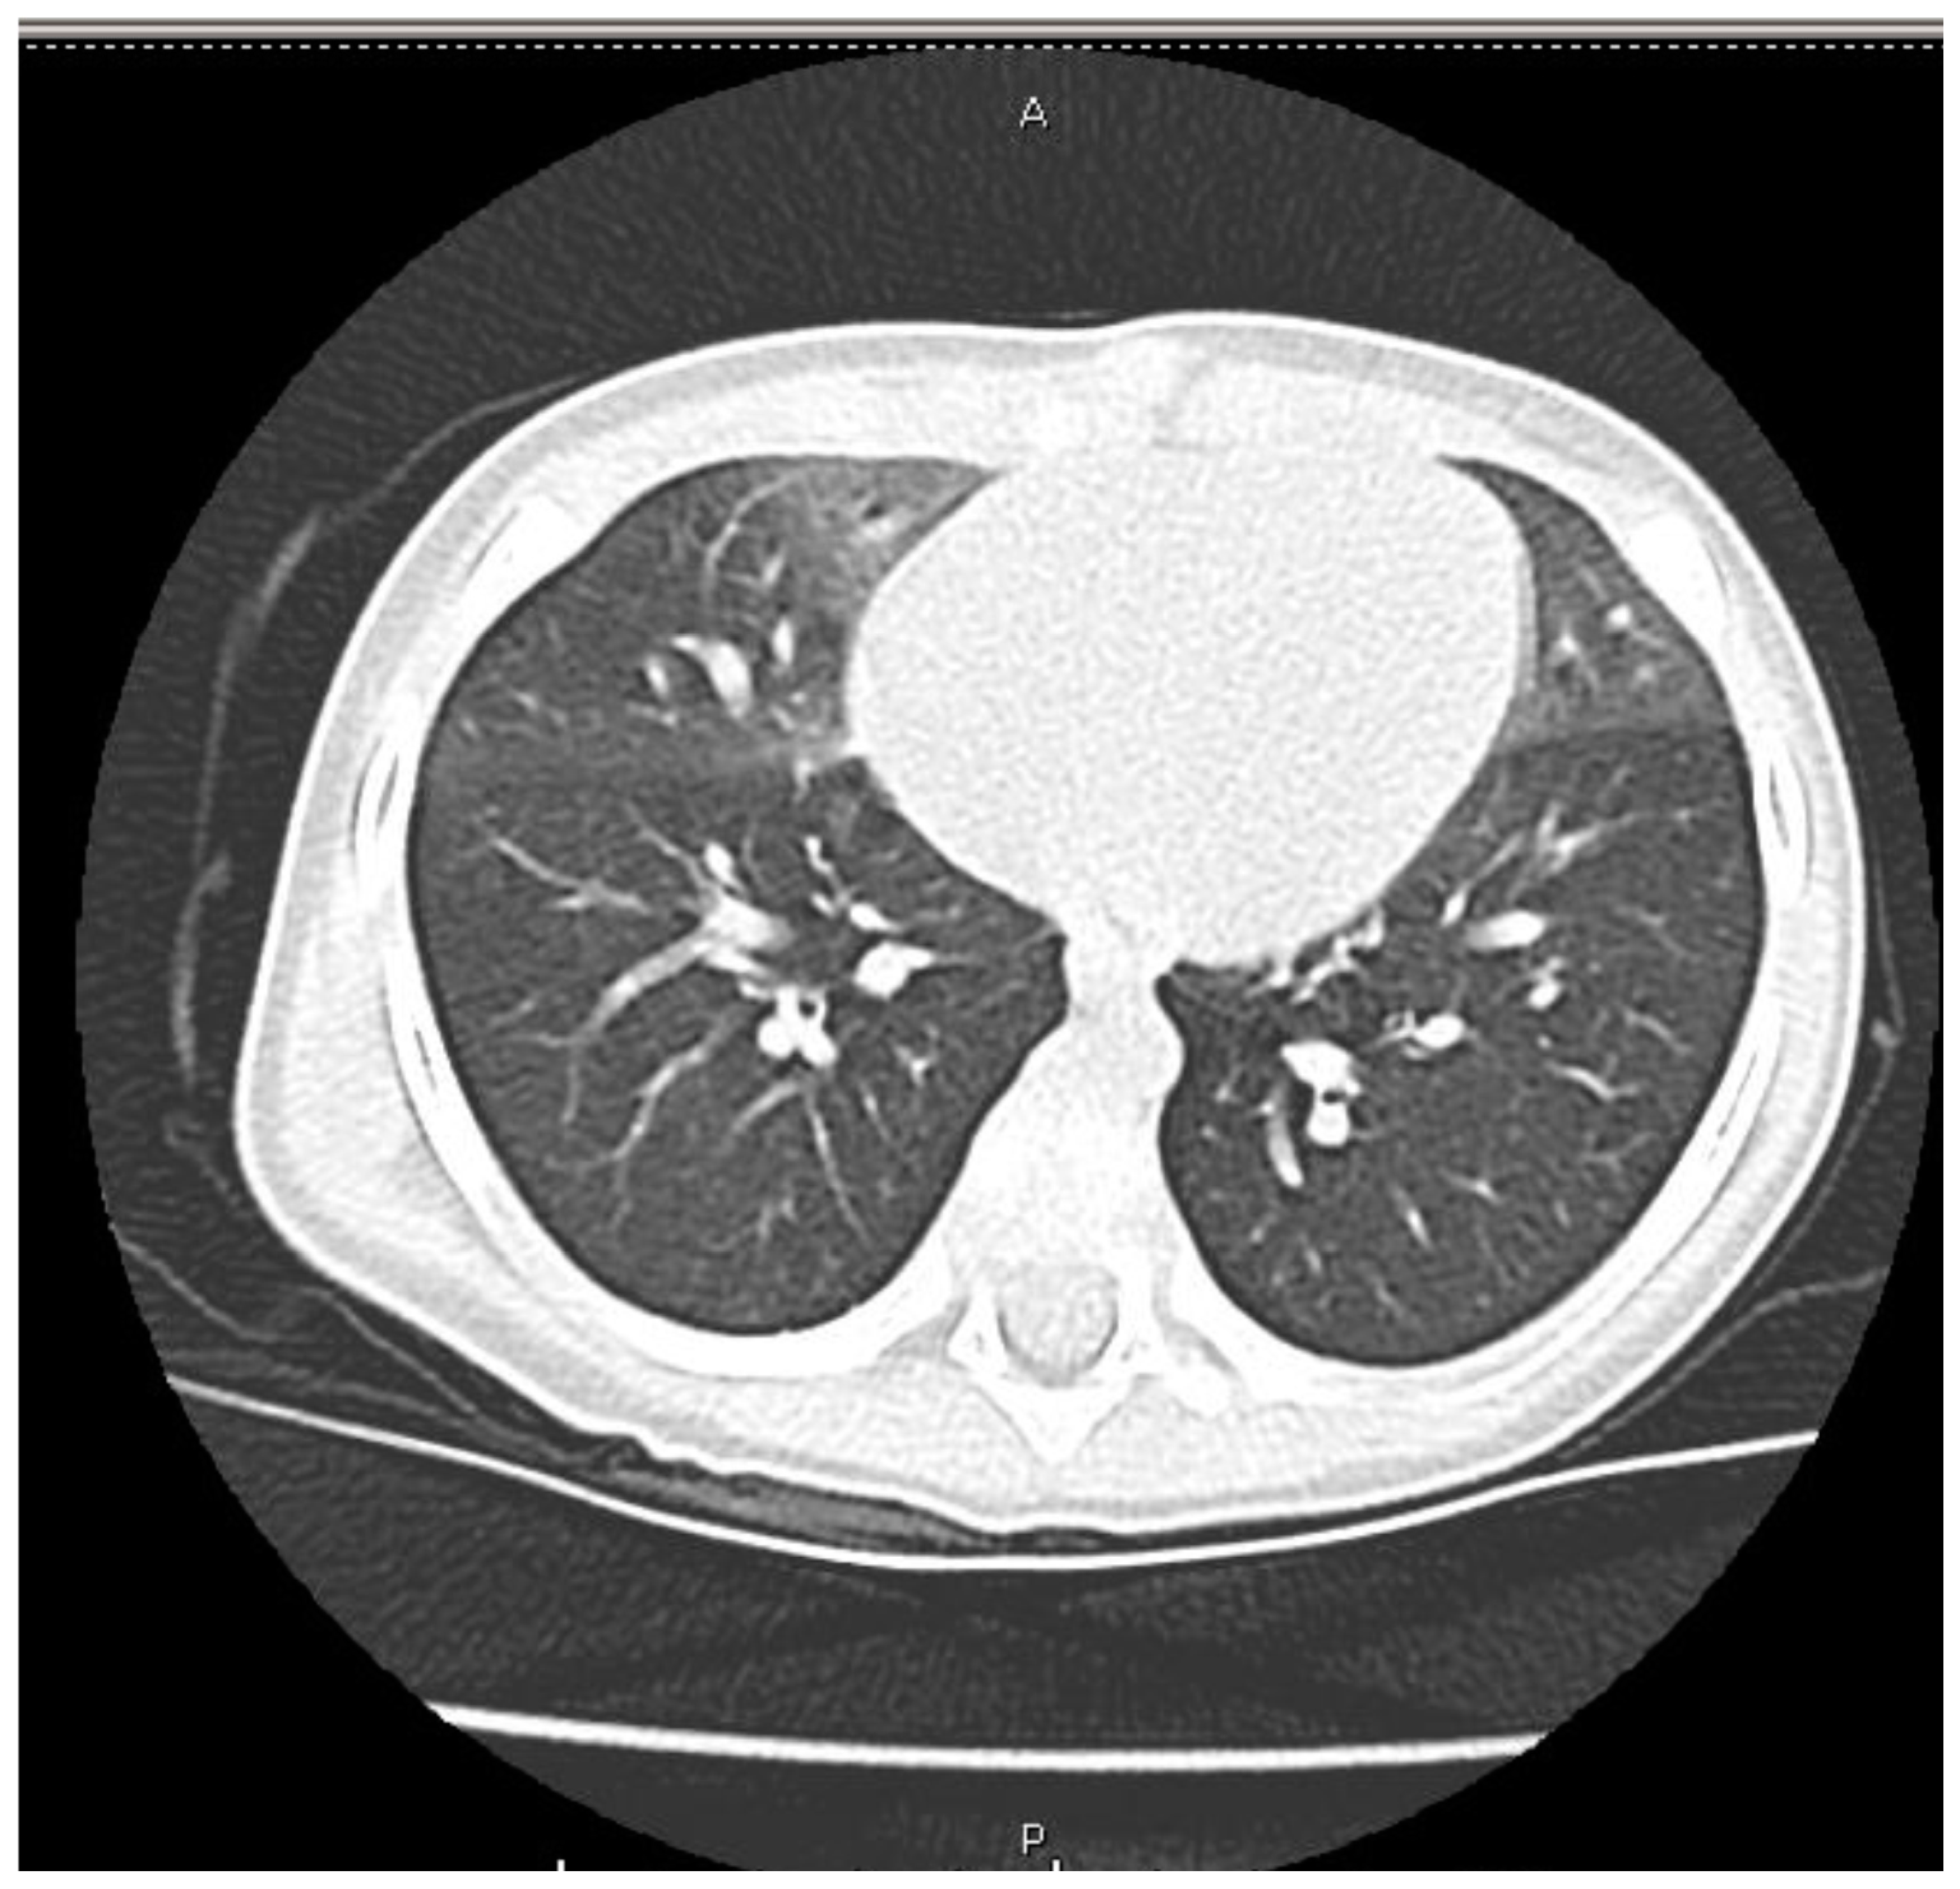

2. Case Presentation

3. Discussion